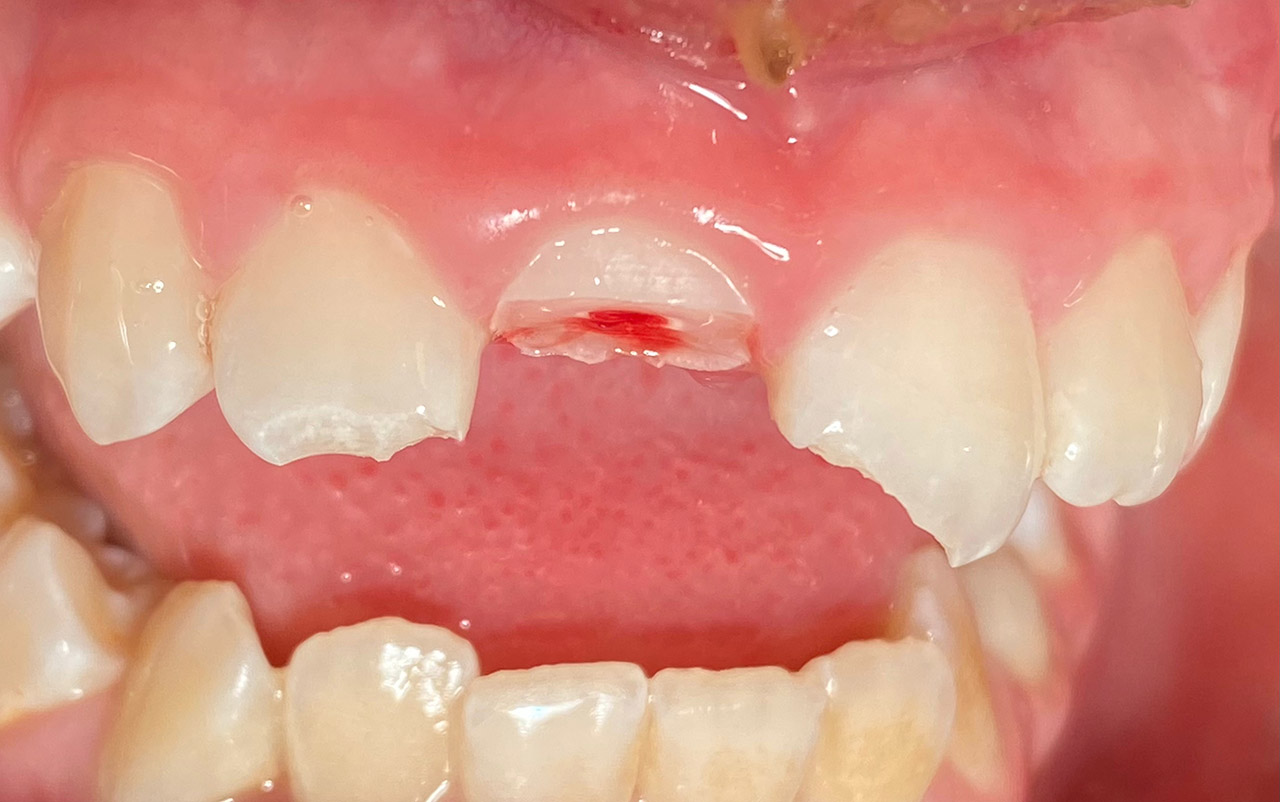

Traumatologie und Endodontie:

Nach Unfall/Sturz mittlerer Schneidezahn auf Gingivaniveau abgebrochen, Pulpa weit eröffnet, beide Nachbarzähne ebenfalls frakturiert.

Erstversorgung: Pulpektomie der Kronenpulpa, MTA, provisorischer Verschluß mit rosa Glasionomerfüllung.

Wiederaufbau der Nachbarzähne mit mitgebrachten (plus 1 Stein) Zahnstücken mit Kunststoff ergänzt und adhäsiv verklebt.

2. Schritt nach Aushärtung von MTA: Entfernung der Kronenpulpa im Bruchstück zur Vermeidung von Verfärbung, Füllung mit Kunststoff.

Adhäsives zementieren des abgebrochenen Zahnstücks.